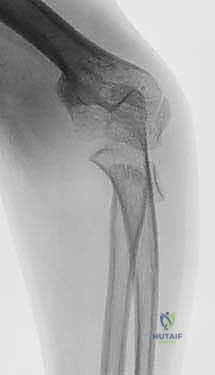

كسر عنق الكعبرة من النوع الثاني (Salter-Harris type II) مع إزاحة واضحة في منطقة الكردوس بالنسبة للمشاشة، وهي حالة تتطلب تقييماً دقيقاً من قبل خبير مثل الأستاذ الدكتور محمد هطيف.

كسر عنق الكعبرة من النوع الأول (Salter-Harris type I)، حيث يمر خط الكسر بالكامل عبر صفيحة النمو، وقد يكون خفياً في صور الأشعة السينية الأولية ويحتاج لعين خبيرة لاكتشافه.